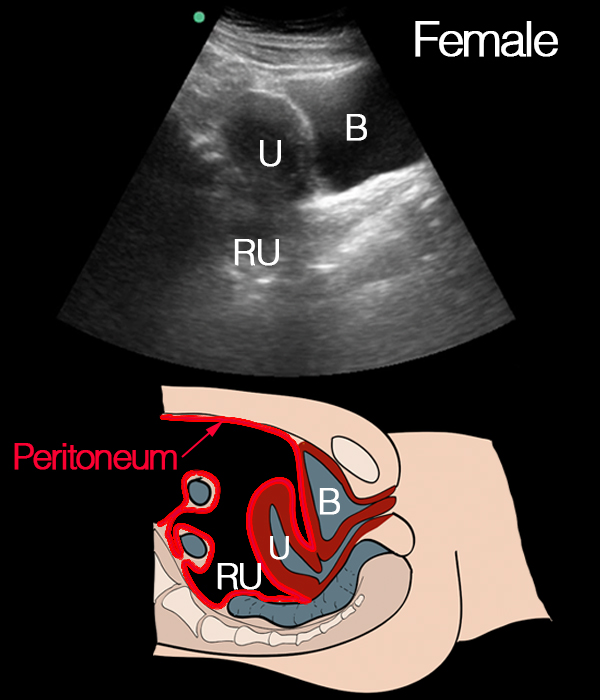

Normal longitudinal view of female pelvis: This longitudinal view shows the normal anatomy of the female pelvis. The bladder (B) is visible, along with the uterus (U) and rectum (RU). This image serves as a reference for identifying these key structures in relation to each other in the longitudinal plane.